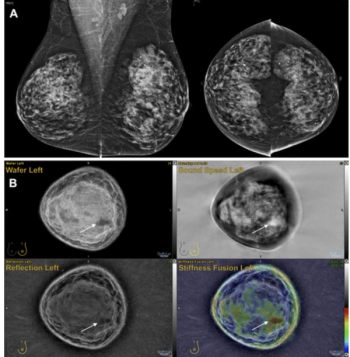

Emerging research suggests that combining full-field digital mammography and whole-breast ultrasound tomography provides superior sensitivity in detecting BI-RADS 4 lesions and superior specificity in diagnosing BI-RADS 3 lesions than mammography alone in women with dense breasts.